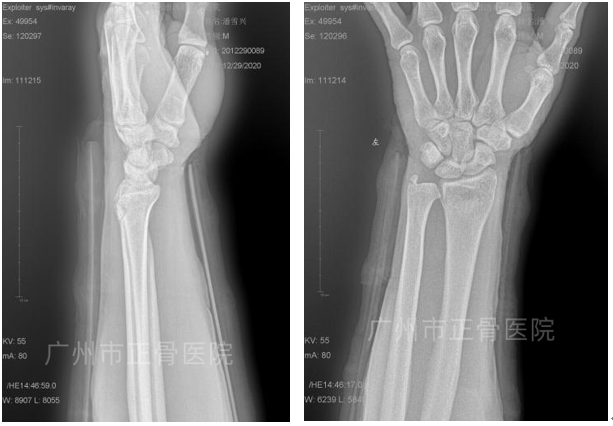

治疗:根据我院桡骨远端骨折诊疗常规,予手法整复夹板外固定治疗。复位后复查X片示骨折对位对线良好。每周返院复查,定期拍摄X线了解骨折情况。1个月后复查X片,提示骨折端骨痂生长。6周后拆除外固定,指导患者功能康复锻炼。8周后腕关节活动基本恢复正常,患处无压痛。

▲复位后,骨折端对位对线良好